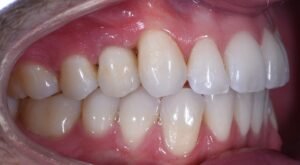

Het resultaat: een herstelde glimlach en meer levenskwaliteit

Na afronding van het traject en het plaatsen van de definitieve kroon kon onze patiënt meteen weer alles doen wat hij gewend was. De nieuwe tand functioneert als een normale tand — de pijn en klachten verdwenen en zijn zelfvertrouwen keerde terug. Een implantaat biedt niet alleen een esthetische verbetering, maar draagt ook merkbaar bij aan uw dagelijkse kwaliteit van leven:

- Verbeterd uiterlijk: Een complete, natuurlijke glimlach versterkt zelfvertrouwen en uitstraling.

- Volledige functionaliteit: Eten, lachen en praten zonder beperkingen.